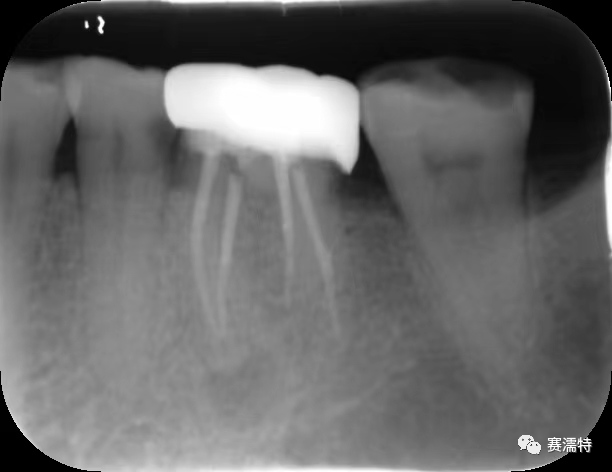

祝自洋老師案例

張云鳳老師案例

張凈玉老師案例

喻剛老師案例

楊艷老師案例

楊超老師案例